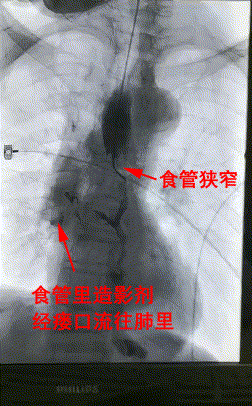

楊阿姨是一名罹患食道癌有5年的患者,近半個月來一進食就嗆咳、嘔吐,滴水難進,而原因就是“食管狹窄+食管氣管瘘”。食管狹窄導緻連喝水都難以進胃,因食管與氣管之間的瘘口,水還流進了肺裏。患者異常消瘦,若不積極治療理論上壽命不超過1個月。

3月28日上午,楊阿姨被送進了介入手術室,李旭丹主任等專家根據術前方案上台施術,先采用飛利浦DSA開展食道造影,明确食道狹窄端及瘘口位置,後經導絲引入食管支架釋放于準确位置。DSA顯示支架成功擴張食管狹窄端并封閉瘘口,順利完成手術。

△術前DSA造影顯示:食管狹窄+食管氣管瘘。